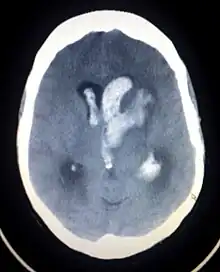

Intraparenchymal hemorrhage can be recognized on CT scans because blood appears brighter than other tissue and is separated from the inner table of the skull by brain tissue. The tissue surrounding a bleed is often less dense than the rest of the brain because of edema, and therefore shows up darker on the CT scan.[30] The oedema surrounding the haemorrhage would rapidly increase in size in the first 48 hours, and reached its maximum extent at day 14. The bigger the size of the haematoma, the larger its surrounding oedema.[31] Brain oedema formation is due to the breakdown of red blood cells, where haemoglobin and other contents of red blood cells are released. The release of these red blood cells contents causes toxic effect on the brain and causes brain oedema. Besides, the breaking down of blood-brain barrier also contributes to the odema formation.[13]